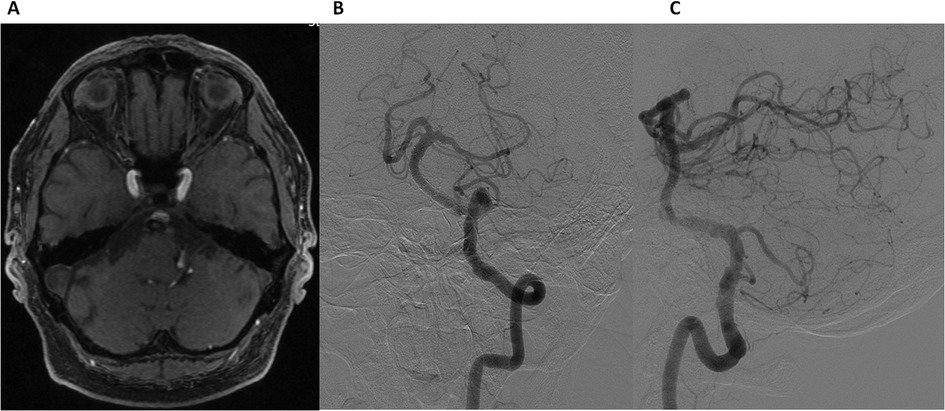

At the 3-month follow-up, the patient reported complete resolution of vertigo, with no new neurological symptoms. Axial TOF MR angiography (Figure 4A) demonstrated thrombosis of the aneurysm, confirming successful flow diversion. DSA (Figures 4B,C) demonstrated the absence of flow within the aneurysm and non-significant residual stenosis (approximately 20%) in the BA. These findings indicate successful flow diversion, effective aneurysm occlusion, and preserved vascular patency. At follow-up, Ticagrelor (90 mg twice daily) was discontinued at 6 months, while Aspirin (100 mg daily) was continued as long-term therapy.

Figure 4. Follow-up at 3 months. Axial time-of-flight (TOF) MR angiography (A) showing aneurysm thrombosis. Digital Subtraction Angiography: Frontal (B) and lateral (C) views of the left vertebral artery demonstrating non-significant residual stenosis in the basilar artery and the absence of flow in the aneurysm.